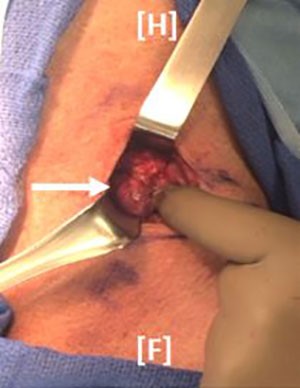

Operative exploration was performed via a transverse cervical Kocher incision. On mobilization of the left thyroid lobe, an approximately 3 cm lesion was identified inferiolateral to the left thyroid (Figure 2), corresponding to the lesion identified on ultrasound and sestamibi scan.

Figure 2: Operative exploration was performed via a Kocher incision. On retraction of the sternothyroid muscle, a lesion (white arrow) was noted lateral to the inferior pole of the left thyroid lobe.

The parathyroid tumor was abnormally adherent to the thyroid gland, but was not pale colored, firm, or fibrotic. Due to concern for possible rupture of the parathyroid tumor during the course of mobilization, as well as for the possibility of parathyroid carcinoma, the left lobe of the thyroid was resected with the enlarged parathyroid gland. The patient was admitted overnight for electrolyte monitoring due to his risk for hungry bone syndrome. Postoperatively, he did well, and was discharged home on 600 mg of elemental calcium three times daily, in addition to daily vitamin D3. His calcium levels decreased from 11.8 mg/dL immediately postoperatively to 9.9 mg/dL on postoperative day one, and then to 8.8 mg/dL on postoperative day three. Pathologic examination demonstrated a 2.6 cm hypercellular parathyroid with decreased intracellular fat (Figure 3), consistent with parathyroid adenoma, with no evidence of malignancy.